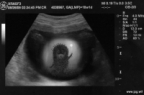

На мой взгляд, это классический аутоиммунный тиреоидит Хасимота.

а узелок зтот типичный "белый принц"сопровождающий этот процесс

А можно поподробнее про "белого принца"? Просто впервые о таком слышу) Хотя картинка похожая мне встречалась, описывала всегда как диффузно-очаговые изменения щитовидной железы, характерные для АИТ.

Я за!Это такой же псевдо узел как я балерина!

Подскажите, данная картина может соответствовать ДТЗ (или это чисто клинико-лабораторный диагноз) ? В заключении все-равно пишем тиреоидит?

Пишу в таких случаях: Диффузные изменения ЩЖ по типу тиреоидита.

Полностью согласен. Диагноз люблю в скобки завернуть -так мягче . И узел в диагноз выношу -ведь говорить что его нет-значит противоречить описываемой картине.

1.Дмитрий! Не понял Вашего ответа. То есть вы против того, что там есть узел или за? Мое мнение, что там классический тиреоидит с наличием обычного узла. Псевдоузел как правило состоит из участков неизмененной по структуре ткани щитовидной железы окруженных гипоэхогенными локусами воспаленных участков.

2.Марина! Не подскажу авторов (но на форуме есть коллеги гораздо подкованнее в этом плане чем я) но нас учили, что токсический зоб это один из немногих лабораторных диагнозов который мы можем поставить при ультразвуковом исследовании. При этом мы увидим значительное повышение васкуляризации ткани щитовидной железы по типу "тиреоидного ада"(на один см3 ткани приходится более 2 сосудов) и увеличение скоростных показателей.

Да, я не вижу в данном случае узла.

"Псевдоузел щитовидной железы"- слышу такое в первый раз! Откуда такие данные?